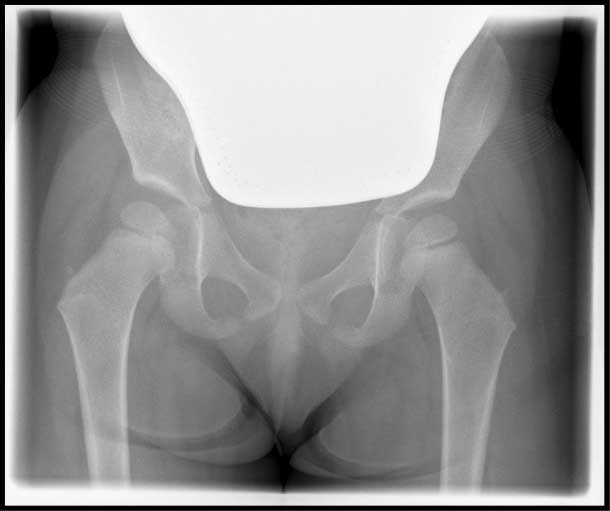

Die linke Hüfte (auf der

rechten Bildseite) steht weiter außen und höher als die Gegenseite in Bezug auf das Becken. Der

Hüftkopf selber ist bei dem Kind noch knorpelig angelegt und auf dem Röntgenbild deshalb nicht

sichtbar.

Die linke Hüfte steht weiter außen und höher als die Gegenseite in Bezug auf das Becken. Der Hüftkopf selber ist bei dem Kind noch knorpelig angelegt und auf dem Röntgenbild deshalb nicht sichtbar.